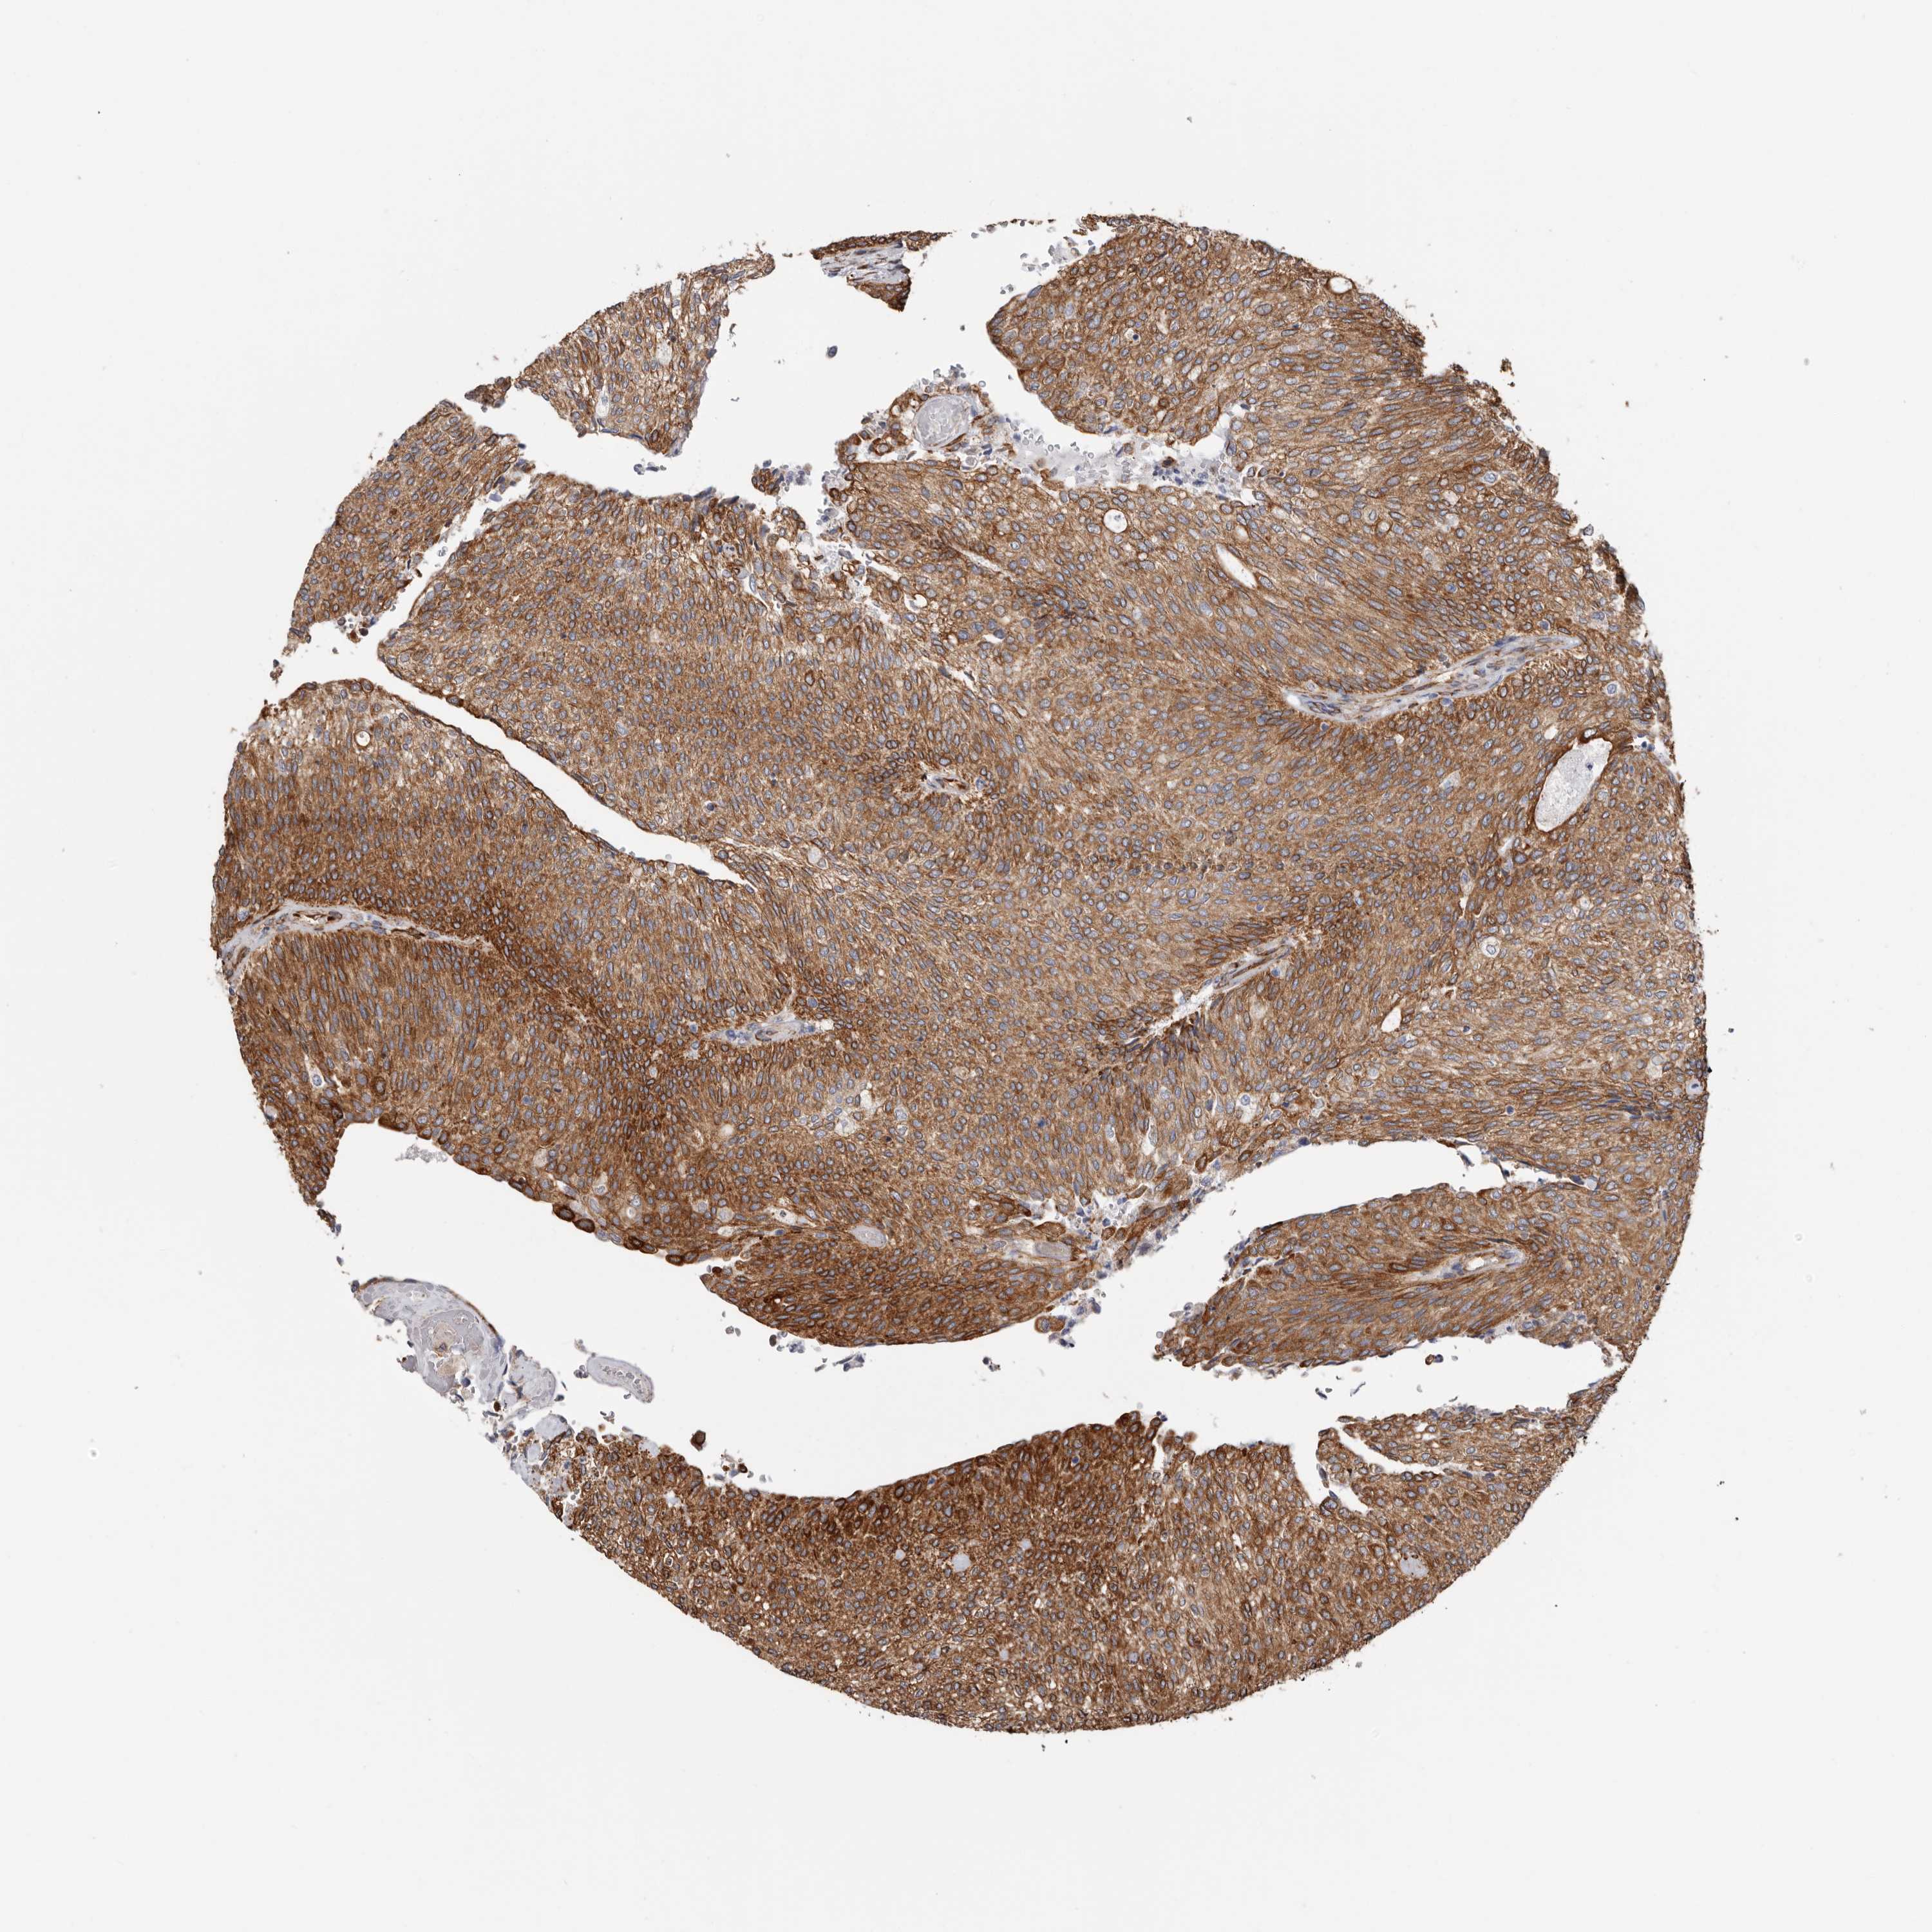

UROTHELIAL CANCER - Protein expressioni

A mouse-over function shows sample information and annotation data. Click on an image to view it in a full screen mode. Samples can be filtered based on level of antibody staining by selecting one or several of the following categories: high, medium, low and not detected. The assay and annotation is described here.

Note that samples used for immunohistochemistry by the Human Protein Atlas do not correspond to samples in the TCGA dataset.

Antibody stainingi

Antibody staining in the annotated cell types in the current human tissue is reported as not detected, low, medium, or high, based on conventional immunohistochemistry profiling in selected tissues. This score is based on the combination of the staining intensity and fraction of stained cells.

Each image is clickable and will lead to virtual microscopy that enables deeper exploration of all samples and also displays staining intensity scores, fraction scores and subcellular localization as well as patient and tissue information for each sample.

Antibody HPA029419

Staining

High

Medium

Low

Not detected

Intensity

Strong

Moderate

Weak

Negative

Quantity

>75%

75%-25%

<25%

None

Location

Nuclear

Cytoplasmic/membranous

Cytoplasmic/membranous,nuclear

Urothelial carcinoma, Low grade

Urothelial carcinoma, High grade